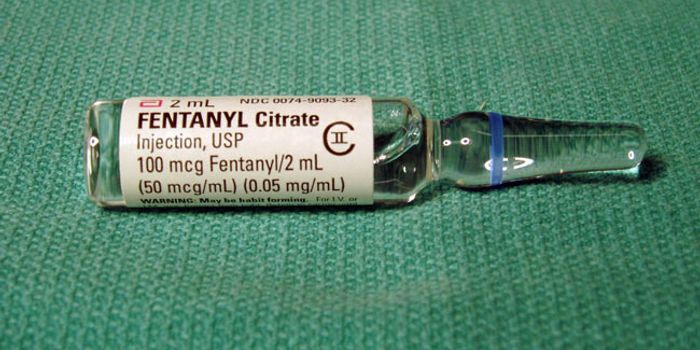

FEB 23, 2016Health & MedicineOpioid addiction is a huge problem, with about 2 million Americans suffering from addiction to prescription pain relieve ...

NOV 26, 2018Health & MedicineAnyone who has experienced severe, chronic pain knows the long process it takes to get a correct diagnosis. Many people ...